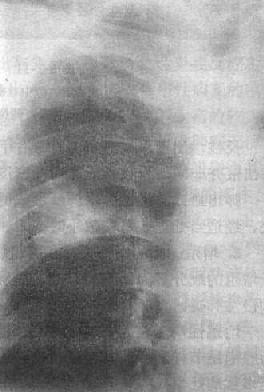

6.空洞与空腔 空洞(cavity)为肺内病变组织发生坏死,坏死组织经引流支气管排出而形成。X线表现为大小与形状不同的透明区(图3-1-13)。见于肺结核的干酪样坏死病变、肺脓肿、肺癌及某些真菌病。空洞壁可由坏死组织、肺脓肿、肺癌及某些真菌病。空洞壁可由坏死组织、肉芽组织、纤维组织、肿瘤组织或洞壁周围的薄层肺不张所形成。依病理变化可分为三种:

(1)虫蚀样空洞:又称无壁空洞,是大片坏死组织内的空洞,较小,形状不一,常多发,洞壁为坏死组织。X线表现为实变肺野内多发小的透明区。轮廓不规则,如虫蚀状。见于干酪性肺炎。

空洞的三种形态

图3-1-13 空洞的三种形态

(2)薄壁空洞:洞壁薄,壁厚在3mm以下,由薄层纤维组织及肉芽组织形成。X线表现为境界清晰、内壁光滑的圆形透明区。一般空洞内无液面,周围很少有实变影。常见于肺结核。

(3)厚壁空洞:洞壁厚度超过3mm。X线上,空洞呈形状不规则的透明影,周围有密度高的实变区。内壁凹凸不平或光滑整齐。多为新形成的空洞。见于肺脓肿、肺结核及肺癌。结核性空洞常无或仅有少量液体,而肺脓肿的空洞内多有明显的液面。癌瘤内形成的空洞其内壁多不规则,呈结节状。